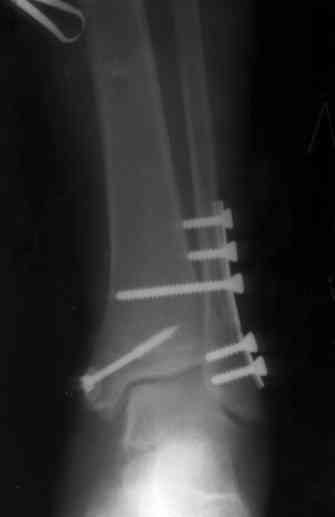

Здесь финальный снимок 73 летней с

сопутствующей шизофренией, латерально бридж

пластину (соединили дистальный конец с диафизом не трогая место перелома) и медиально перкутанно

двумя шурупами. В этам случае без гипса не

обойтись.

Точно, для идеальной репозиции надо открыть передний и задний углы медиальной лодыжки,

сделать ревизию сустава, очистить, убрать интерпозицию, потом только зафиксировать.

Как заметил, по рентгенограмме медиальная лодыжка не очень идеально репонирована. Больная кроме шизофрении страдала другими соматическими заболеваниями, и во время операции от анестезиолога получил рекомендацию поторопиться, поэтому решили закрыто, а так тенденция лечить

открытым методом.